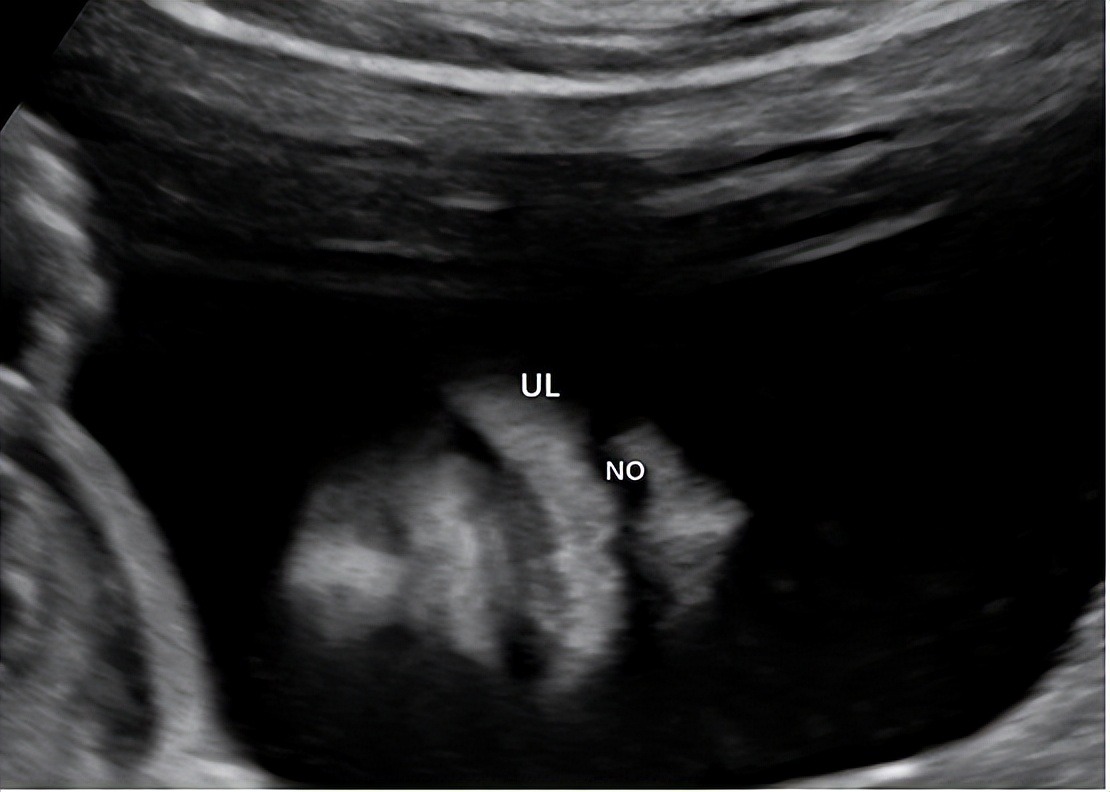

2.鼻唇冠状切面

切面要求:显示双侧鼻孔、上唇(图2)。

观察内容:双侧鼻孔对称,上唇连续。

图2 孕22 周上唇冠状切面 显示双侧鼻孔、上唇(NO:鼻孔;UL:上唇)